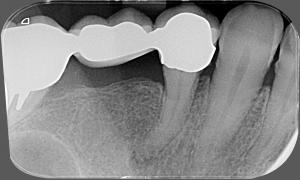

Pred zákrokom

Zub s veľkým zápalom okolo hrotu koreňa

Po zákroku

Zaplnenie koreňového kanálika s viditeľne zmenšeným zápalom